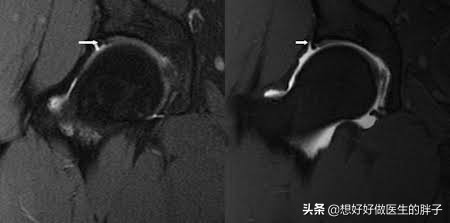

这并不意味着已经进行了X射线检查开yun体育app入口登录,这完全消除了患者的问题。有时,X射线上不会出现早期病变或髋关节的软组织问题,因此我们还建议髋部疼痛患者如果您患有单侧髋关节疼痛,甚至应该执行单侧髋关节MMI。因为单个髋关节核磁检查可以更好地确定髋关唇是否为撕裂。